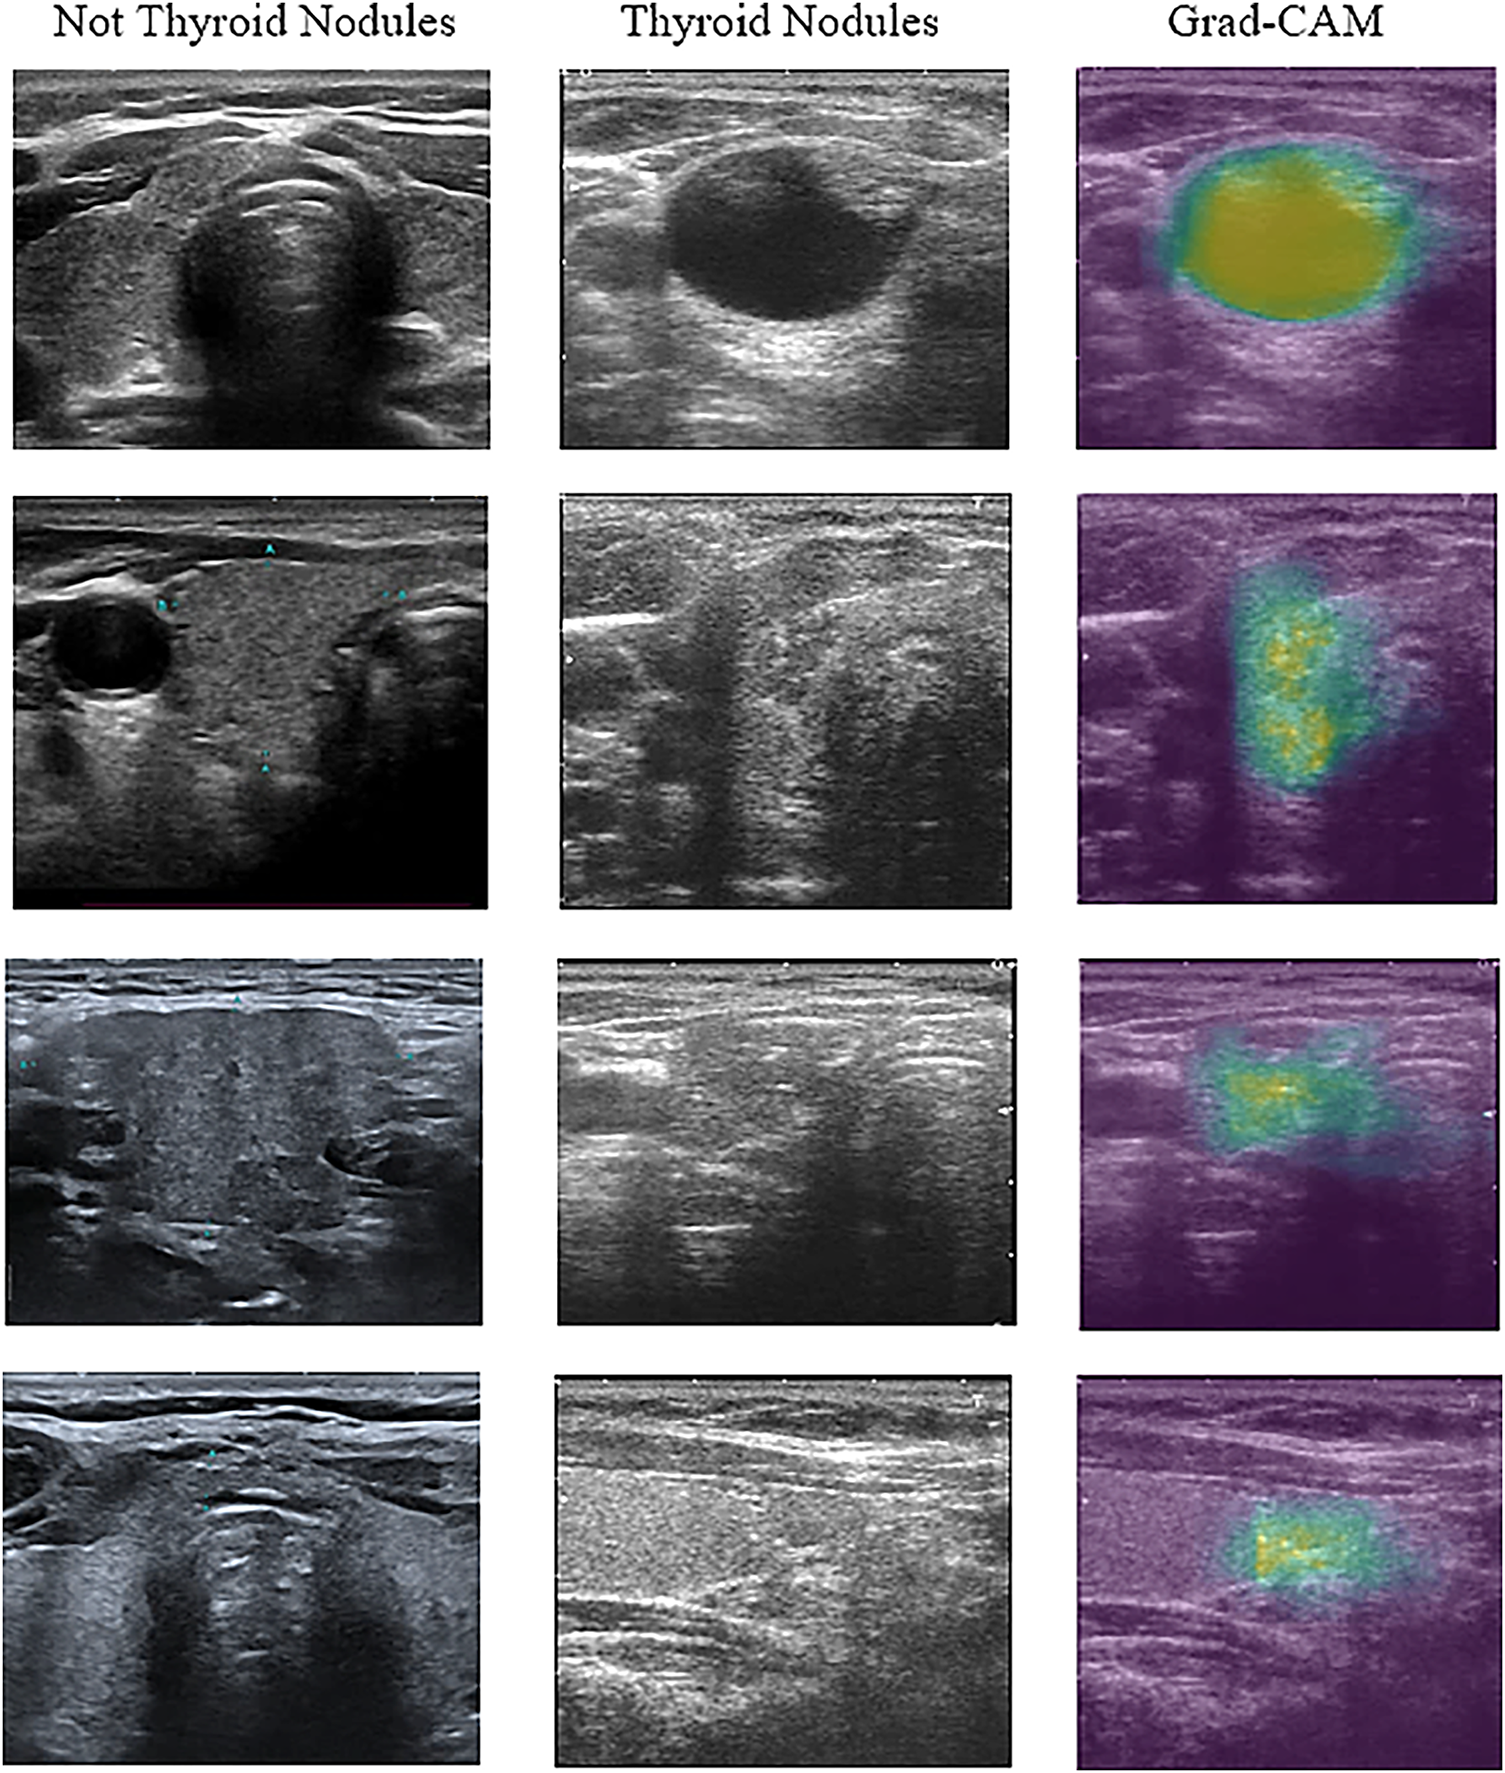

Fig. 6 shows some of the selected ultrasound images that were classified using the proposed model. All ultrasound images were classified correctly regarding the presence of thyroid nodules in them. Images containing either a lobe or part of the lymph were classified as non-thyroid.

Figure 6: Example of ultrasound image classification result

As shown in Fig. 6, the images were visualised after being processed by the model. The first column in the figure represents the images that the proposed model predicted without thyroid nodules. The second column shows the image with thyroid nodules, and the third column shows the 3D CNN model that localised thyroid nodules and distinguished the nodular regions using the gradient-weighted CAM (Grad-CAM) technique. This technique offers critical interpretability by highlighting the specific anatomical areas that most significantly influenced the detection decision.